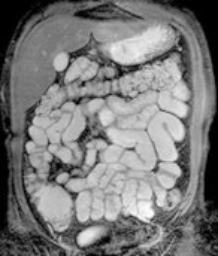

Der Schwerpunkt der MRT liegt in der Darstellung von Weichteilstrukturen, das heißt vor allem von nicht-knöchernen Strukturen. Die häufigsten Einsatzbereiche der Magnetresonanztomographie (MRT) sind die Diagnostik von Erkrankungen der Oberbauchorgane (Leber, Nieren, Nebennieren, Bauchspeicheldrüse), der Lymphknoten, der Gelenke und Muskeln, des Gehirns (inklusive der Gefäße), des Darms, des Herzens und der Gefäße oder auch der Brustdrüse (Mamma). Insbesondere lassen sich Entzündungen oder gut- bzw. bösartige Tumoren hervorragend darstellen. Da die Lunge vorwiegend Luft beinhaltet und die Luft kein Signal im MRT gibt, eignet sich hierfür das CT deutlich besser zur Darstellung.